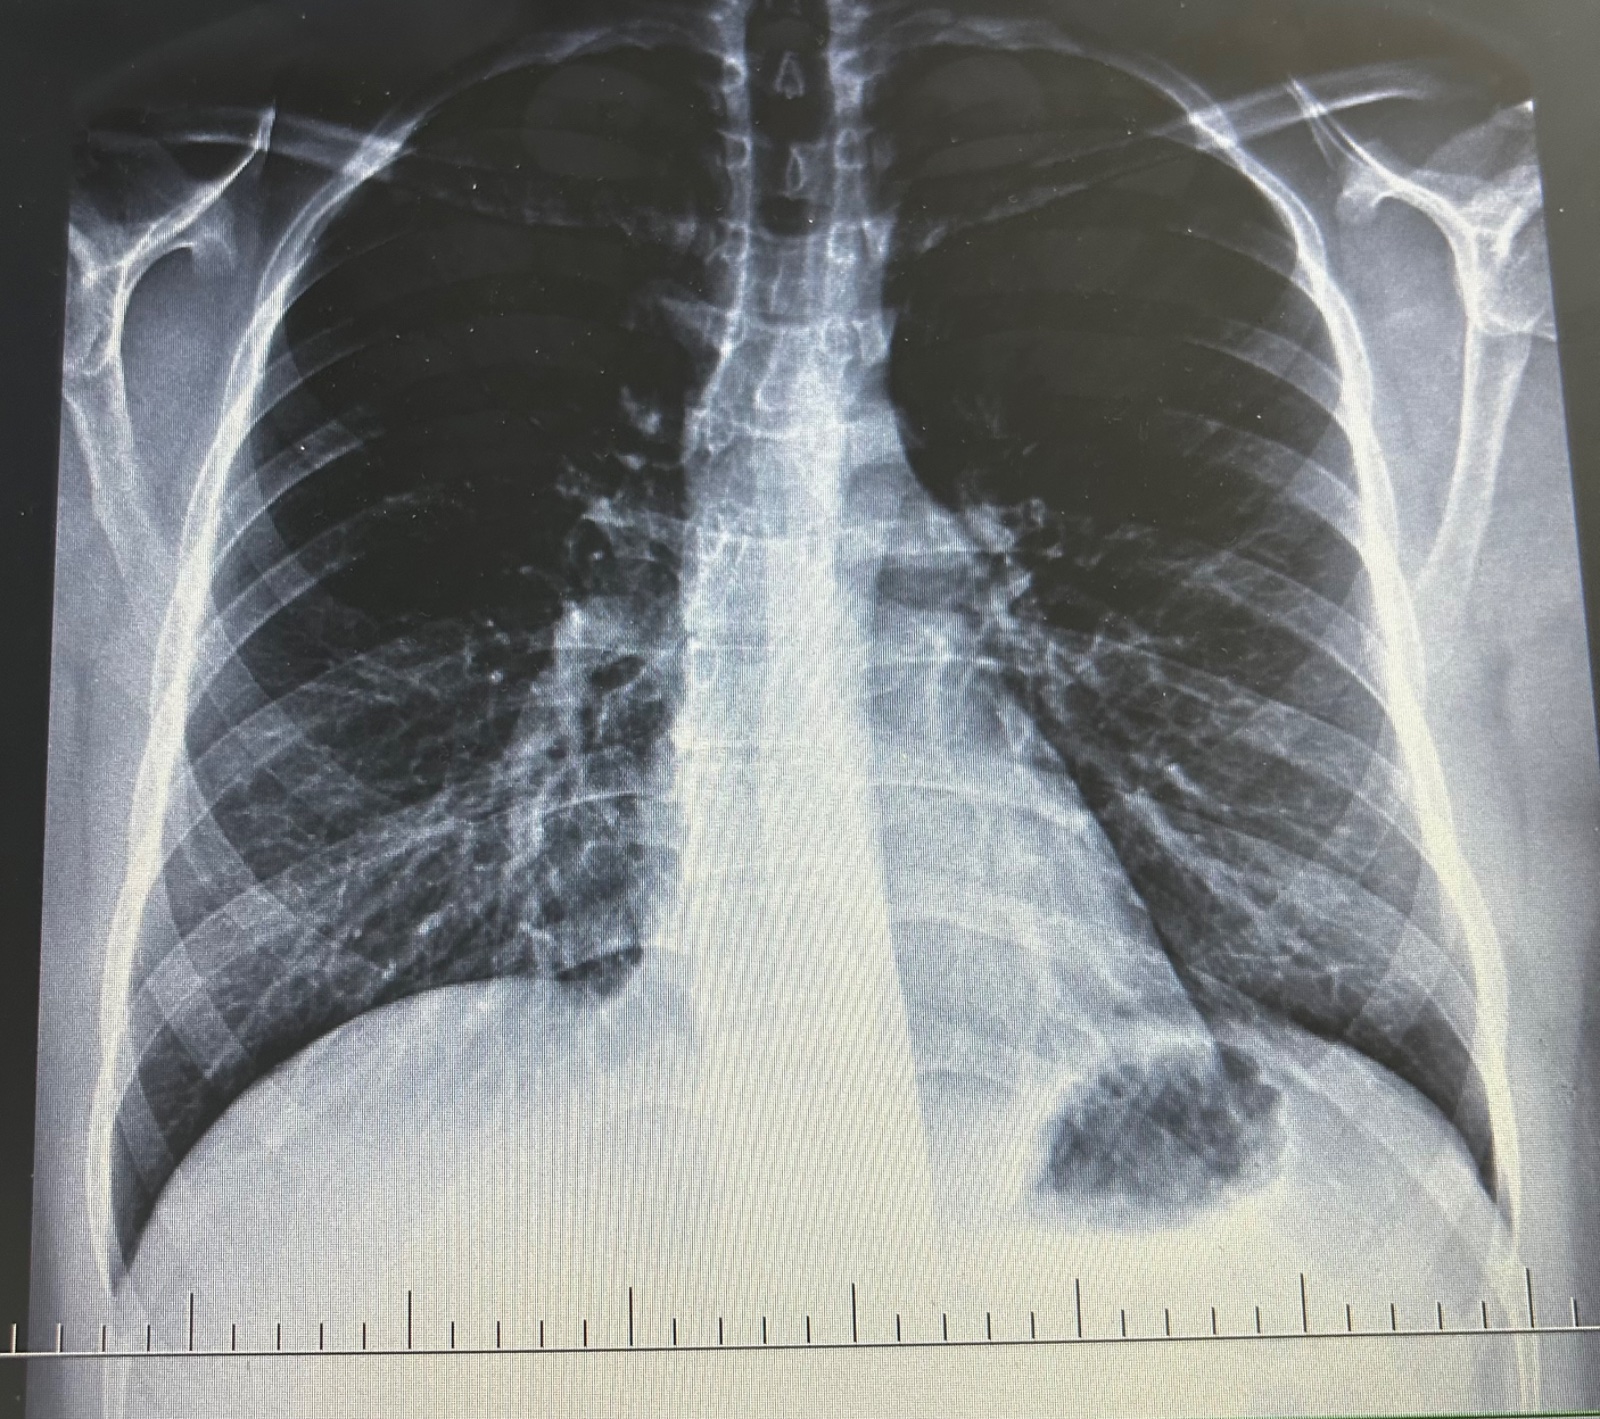

Čo znamená čierny flak na röntgenovom snímku?

Dobry deň, chcem sa spytat je tu niekto kto sa stretol z ciernym dobre ohranicenym flakom na rtg snimke a vyzna sa do rtg snimky? čo to znamena može to byt nadorove? lebo plucny lekar napisal do spravy že bez nalezu ale njaky nalez tam predsa je podla snimku

@dienes22 ano vzduchova bublina

Keby to bol nádor tak to by bol naozaj slepý radiológ, keby napíše že bez nálezu 🙈

Nador bude biely, cierny je vzduch, tazko povedat, co si videla